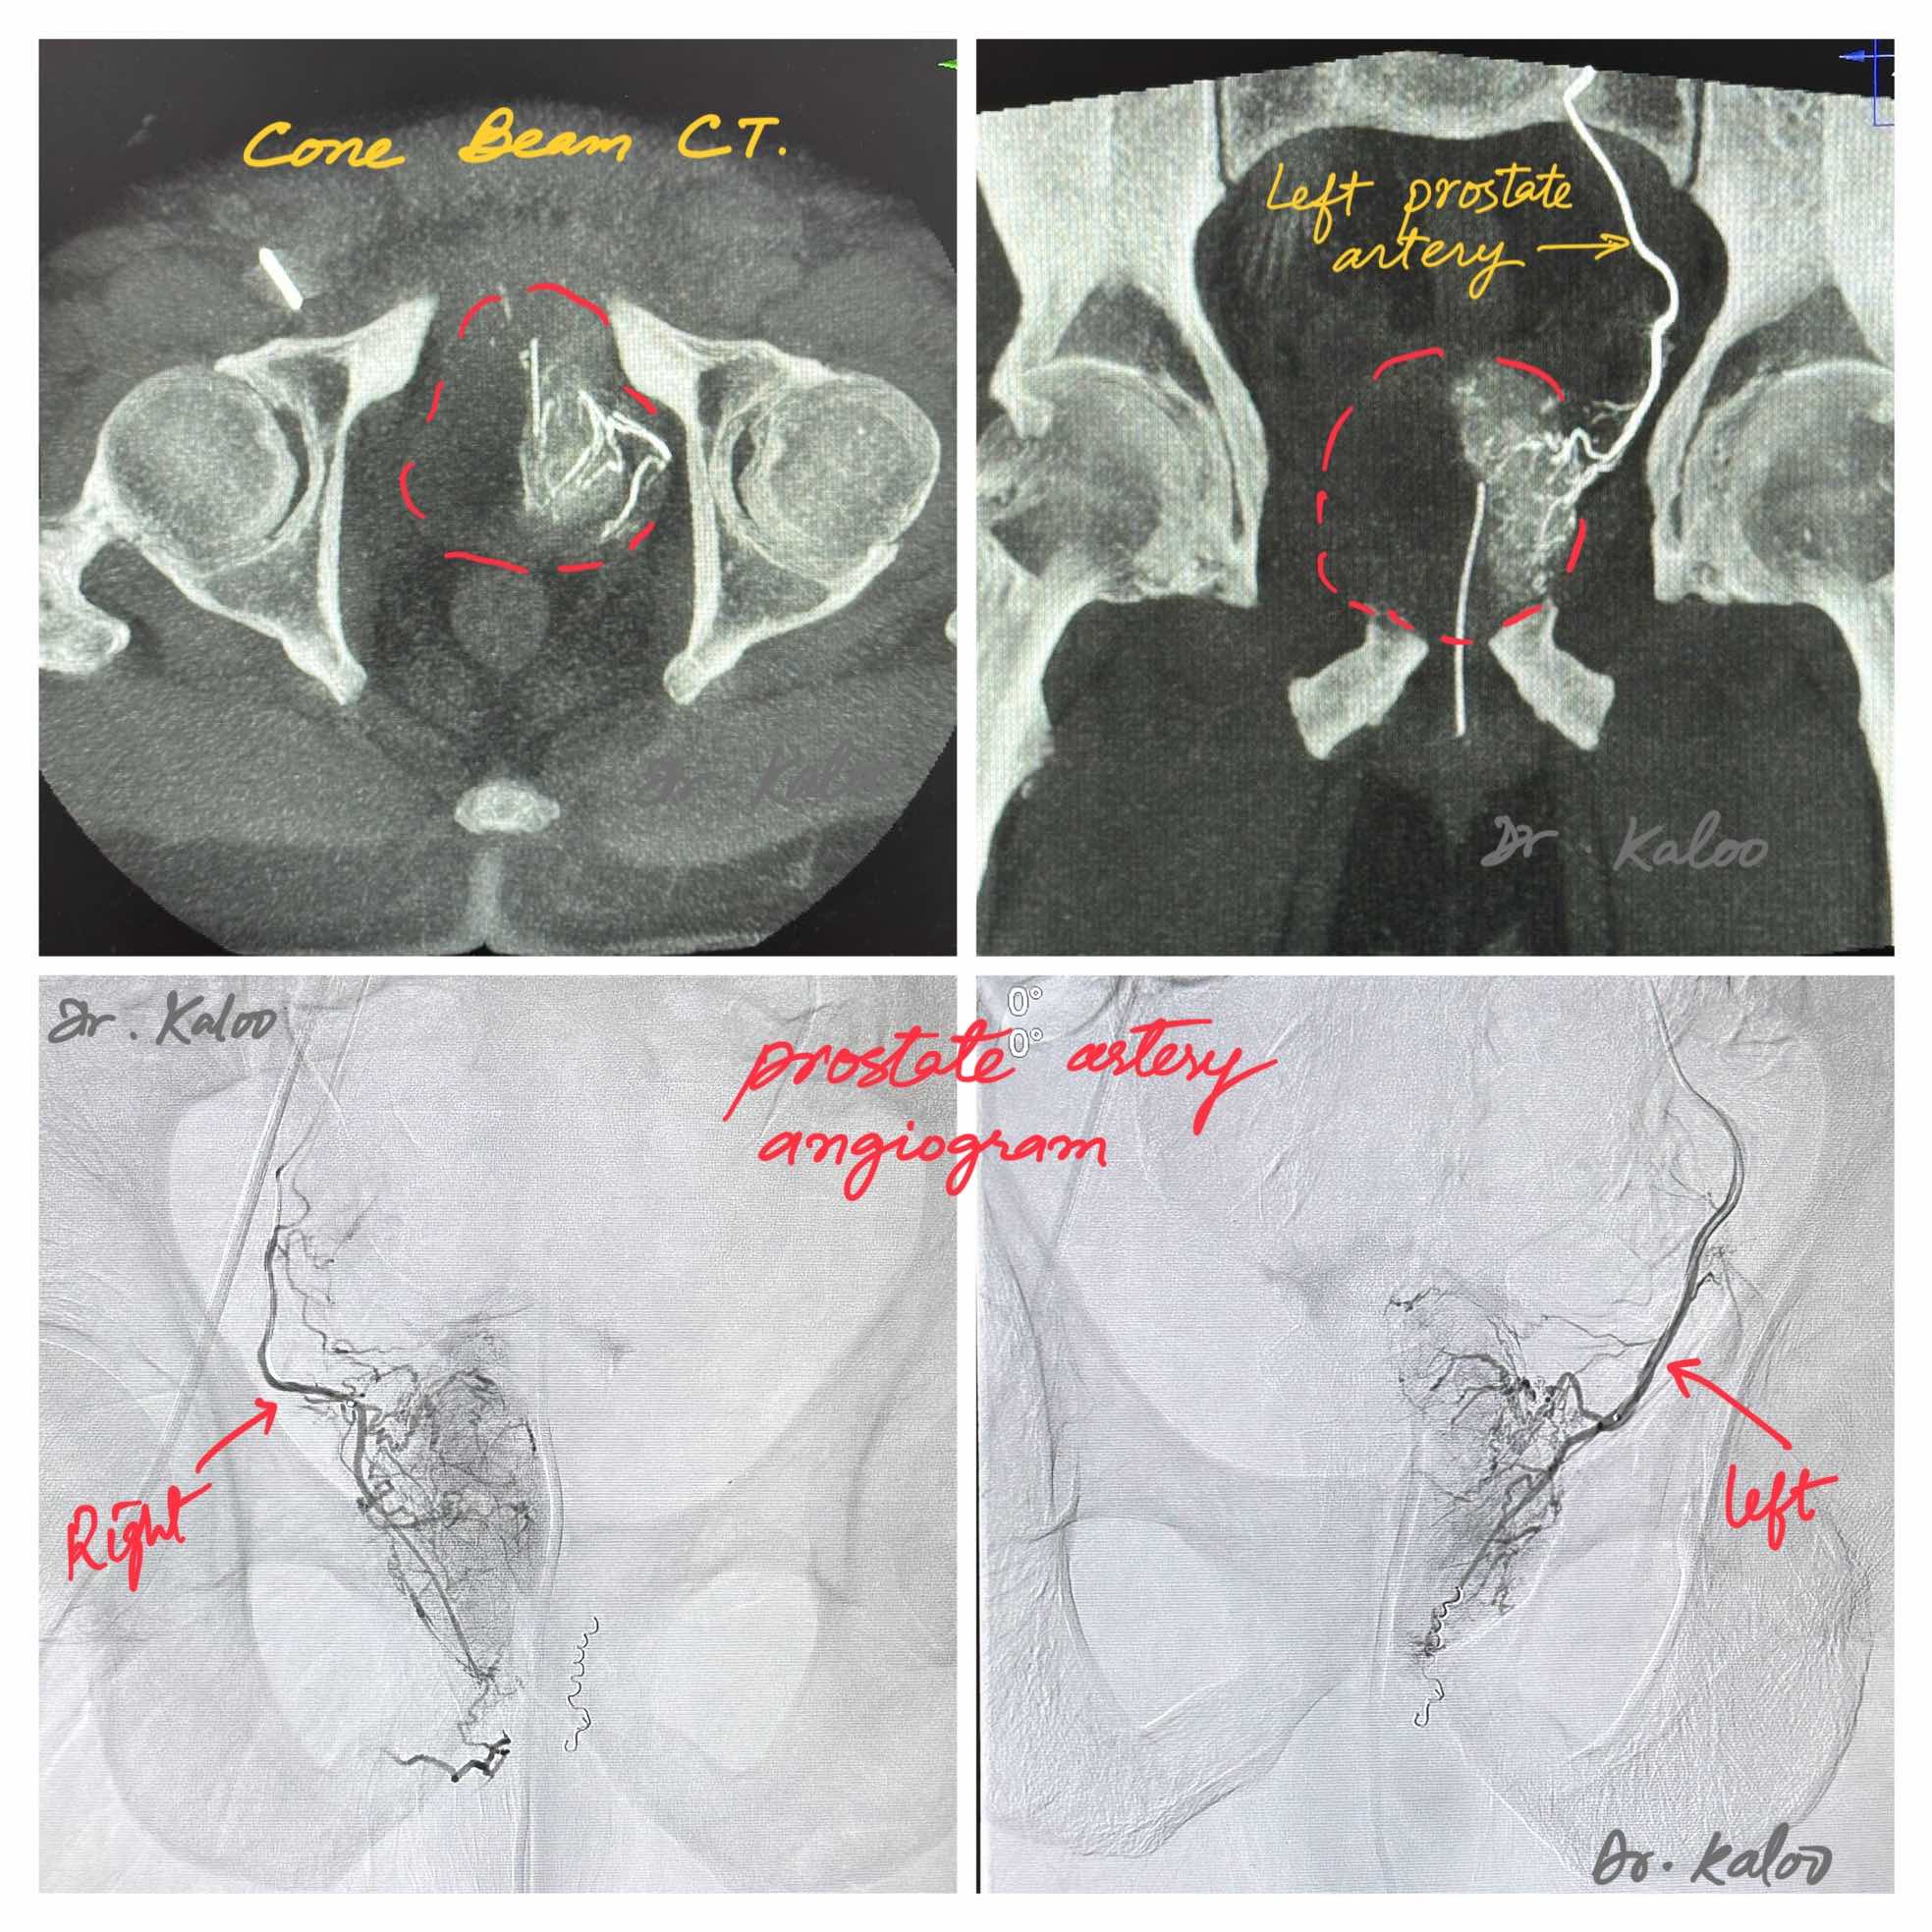

A. PAE procedure is done in an angiography suite. Medical imaging is used to guide a tiny catheter into the arteries that supply blood to the prostate. Once in place, tiny particles are injected through the catheter that block these arteries, thus reducing blood flow to the prostate. This reduction in blood flow causes the prostate to shrink, providing relief to the patient.